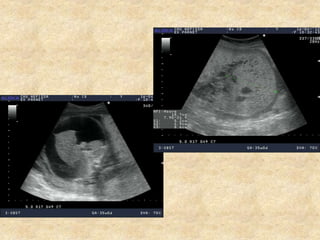

Aspect et volume de la vessie

Aspect des reins

Aspect et volumede la vessie Aspect des reins